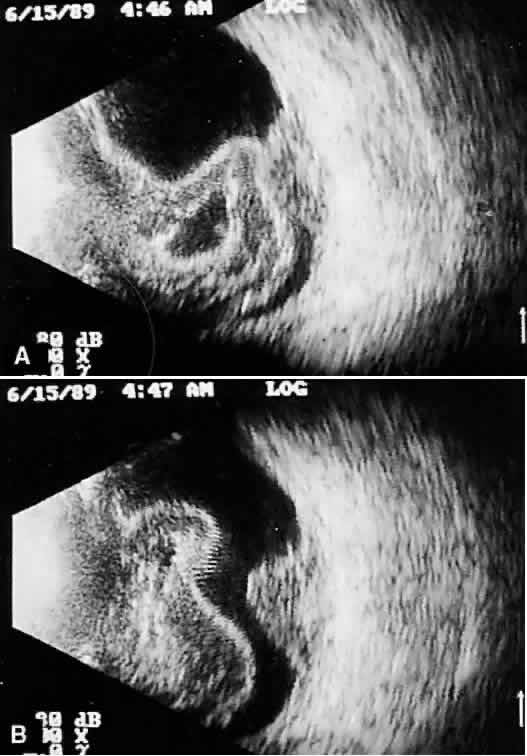

tissue characterization. The B-scan image, a two-dimensional crosssectional display of the globe and orbit, is more easily interpreted than A-scan, especially by examiners familiar with interpretation of ophthalmic pathology, where microscopic and gross crosssectional evaluation of the globe and orbit are routine and often topographically similar to B-scan cross-sections. Several concepts are critical to accurate interpretation of B-scans. These concepts, although relatively easy to define, require considerable experience before the examiner feels comfortable with diagnosis in opaque media situations. These concepts are real time, gray scale, and threedimensional thinking. Real time refers to the display of motion or movement during B-scan imaging. This capability is one of the greatest advantages of B-scan. Differences in mobility of a variety of movable intraocular abnormalities can be easily detected. For example, the rapid movement of vitreous hemorrhage is usually easy to appreciate and differentiate from the slower, undulating movements of a recent, rhegmatogenous retinal detachment. On occasion, movement of intraocular structures can be used for detecting abnormalities that lie immediately behind vitreous opacification and may be seen only when the vitreous opacities are moved away from the ocular wall, set in motion by command voluntary movements of the patient's globe (Fig. 5). Gray scale refers to the variable gray tone of display screen echoes. Strong returning signals (echoes) appear white, whereas weaker reflections are seen as gray, the shade depending on echo strength. Examples of strong reflectors of sound include retinal tissue, sclera, and calcifications of any type (Fig. 6). Weaker echoes from clotted or clumped cells within the vitreous are usually easy to differentiate from the stronger reflectors of sound (Fig. 7). Grading of echo strength may be performed only when the examining ultrasound beam is perpendicular to the object of interest, ensuring the strongest possible reflections. However, in the world of ultrasound interpretation, there are many exception to the rules. Tissues that are usually mild reflectors of sound, such as hemorrhage, can at times appear quite strong, especially in complex or multiple pattern disorders, as frequently occur in severe ocular trauma. These apparent inconsistencies often cause misinterpretation by the novice. With experience obtained by multiple examinations, careful follow-up, and clinical correlation whenever possible, diagnostic acumen rapidly improves.